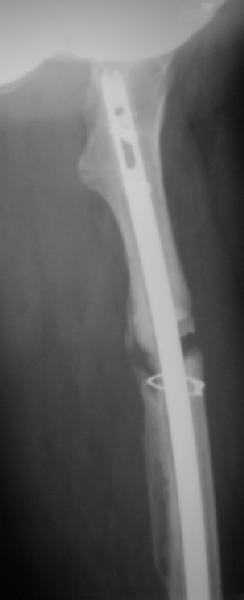

Пациент попал под наше наблюдение через 3 недели после первого остеосинтеза (фото 1). Учитывая, нестабильность остеосинтеза, выстоящий стержень закрыто перештифтовали (фото 2), через 3 месяца динамизация. К 5 месяцам имели укорочение 2 см, при том, что динамический винт стал статическим. От дальнейшей динамизации отказались, учитывая наличие контакта между фрагментами и возможность прогрессирования укорочения. К 1,5 года сращение не достигнуто (фото 3). Удалили гвоздь, выполнили дистракционный остеосинтез с целью стимуляции остеогенеза и компенсации укорочения (фото 4), потом закрыто перештифтовали после рассверливания (фото 5). На сегодняшний день, через 4 месяца после последней операции (фото 6) признаков регенерата нет, длина восстановлена, ходит без дополнительной опоры.